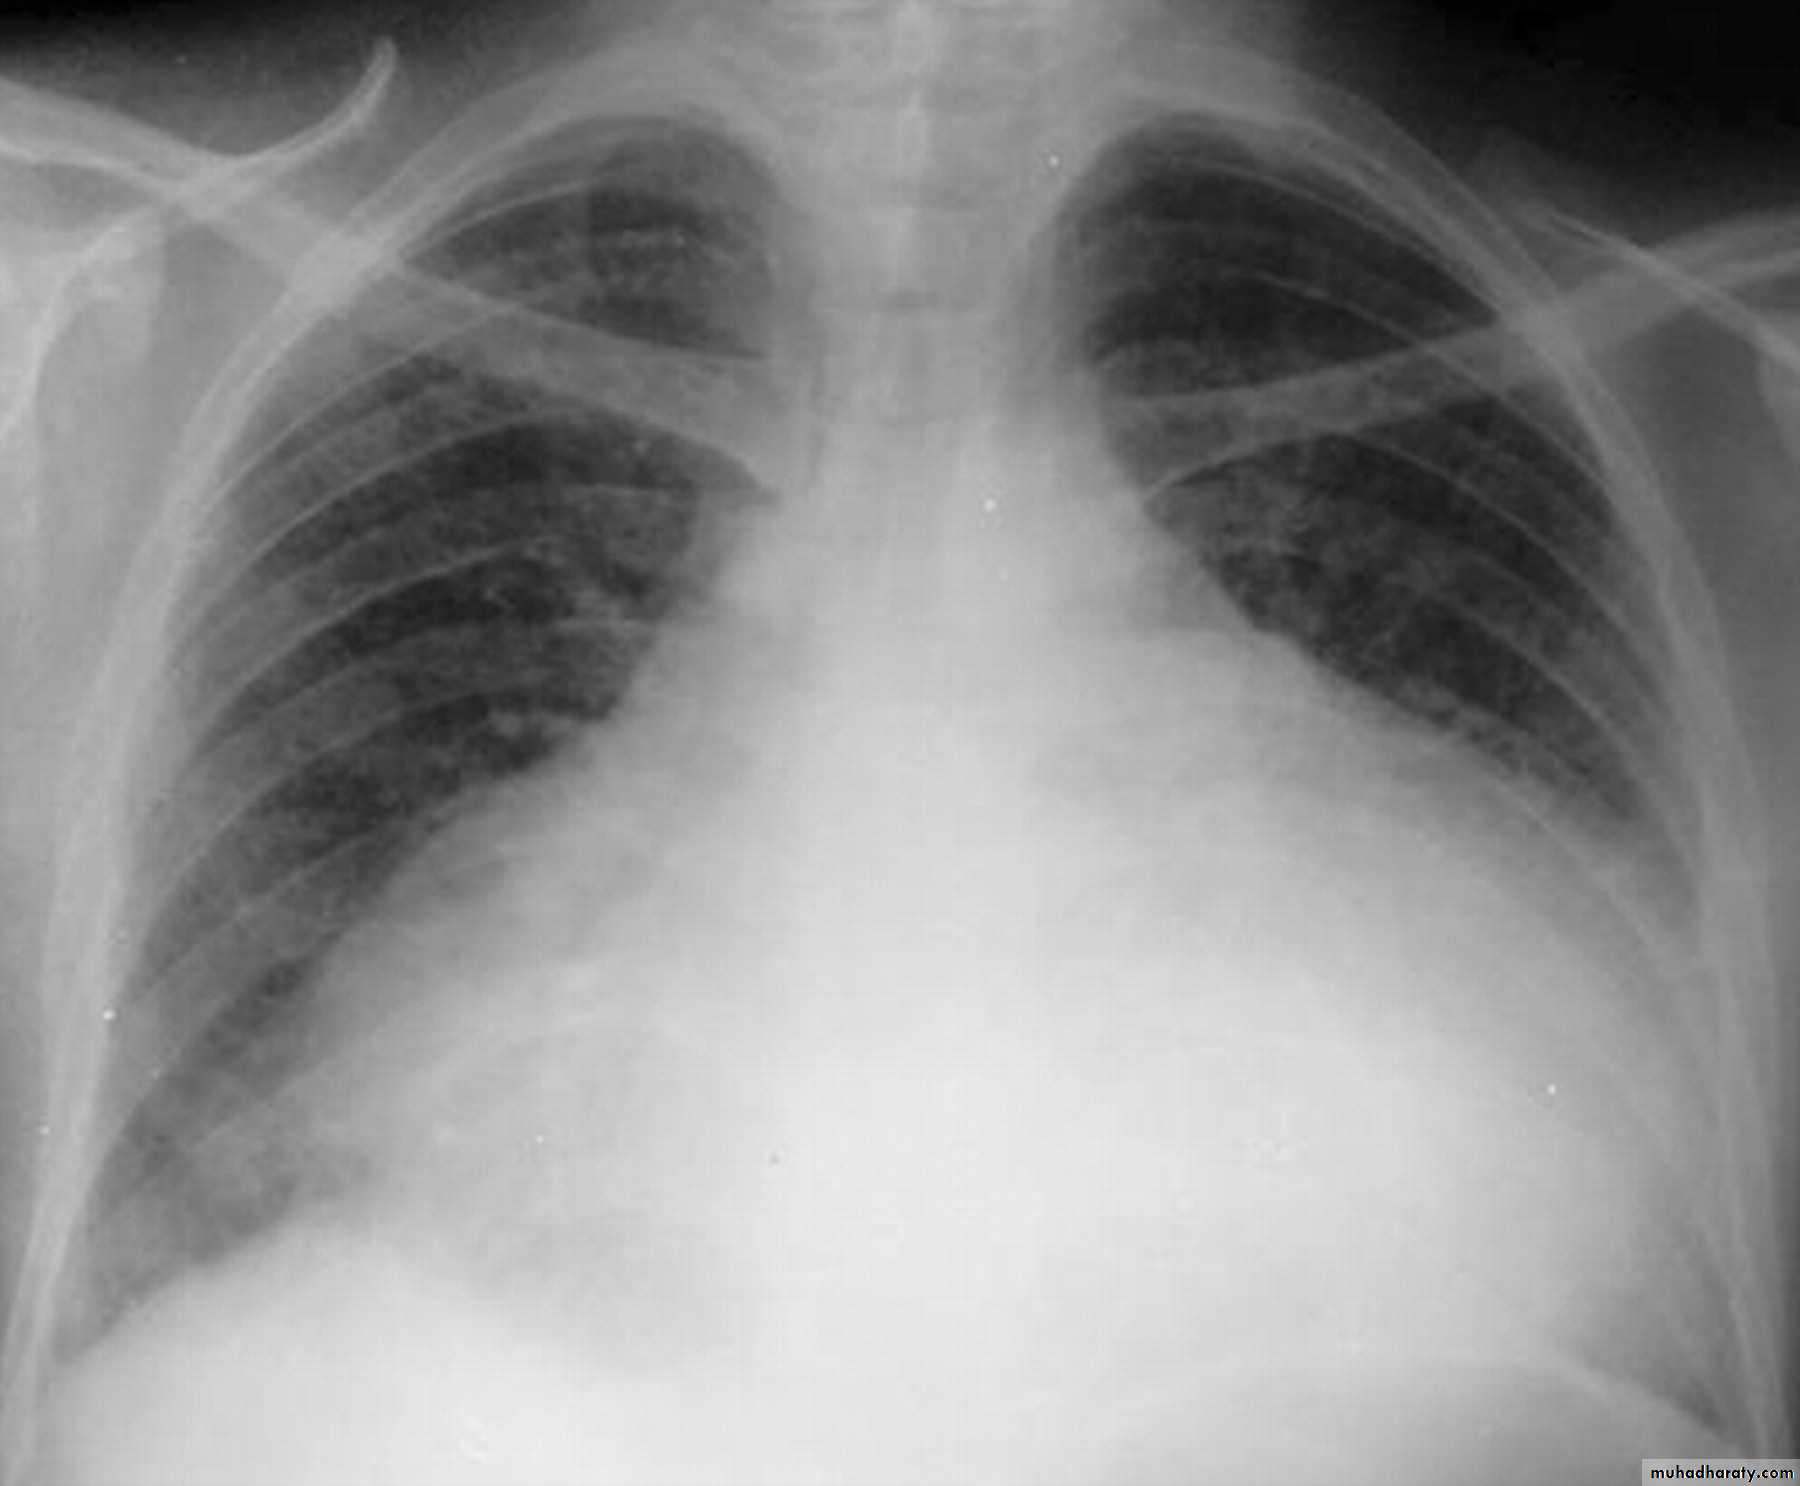

Mitral valve disease

Radiographic featuresPlain film

Typical radiographic features of mitral regurgitation include :

frontal projection

1.left atrial enlargement

convexity or straightening of the left atrial appendage just below the main pulmonary artery (along left heart border)

2.double density sign: the right side of the enlarged left atrium pushes into the adjacent lung and creates an addition contour superimposed over the right heart

3.elevation of the left main bronchus and splaying of the carina

4.upper zone venous enlargement due to pulmonary venous hypertension

5.left ventricular enlargement is also eventually present due to volume overload

6.Features of pulmonary oedema may also be present.